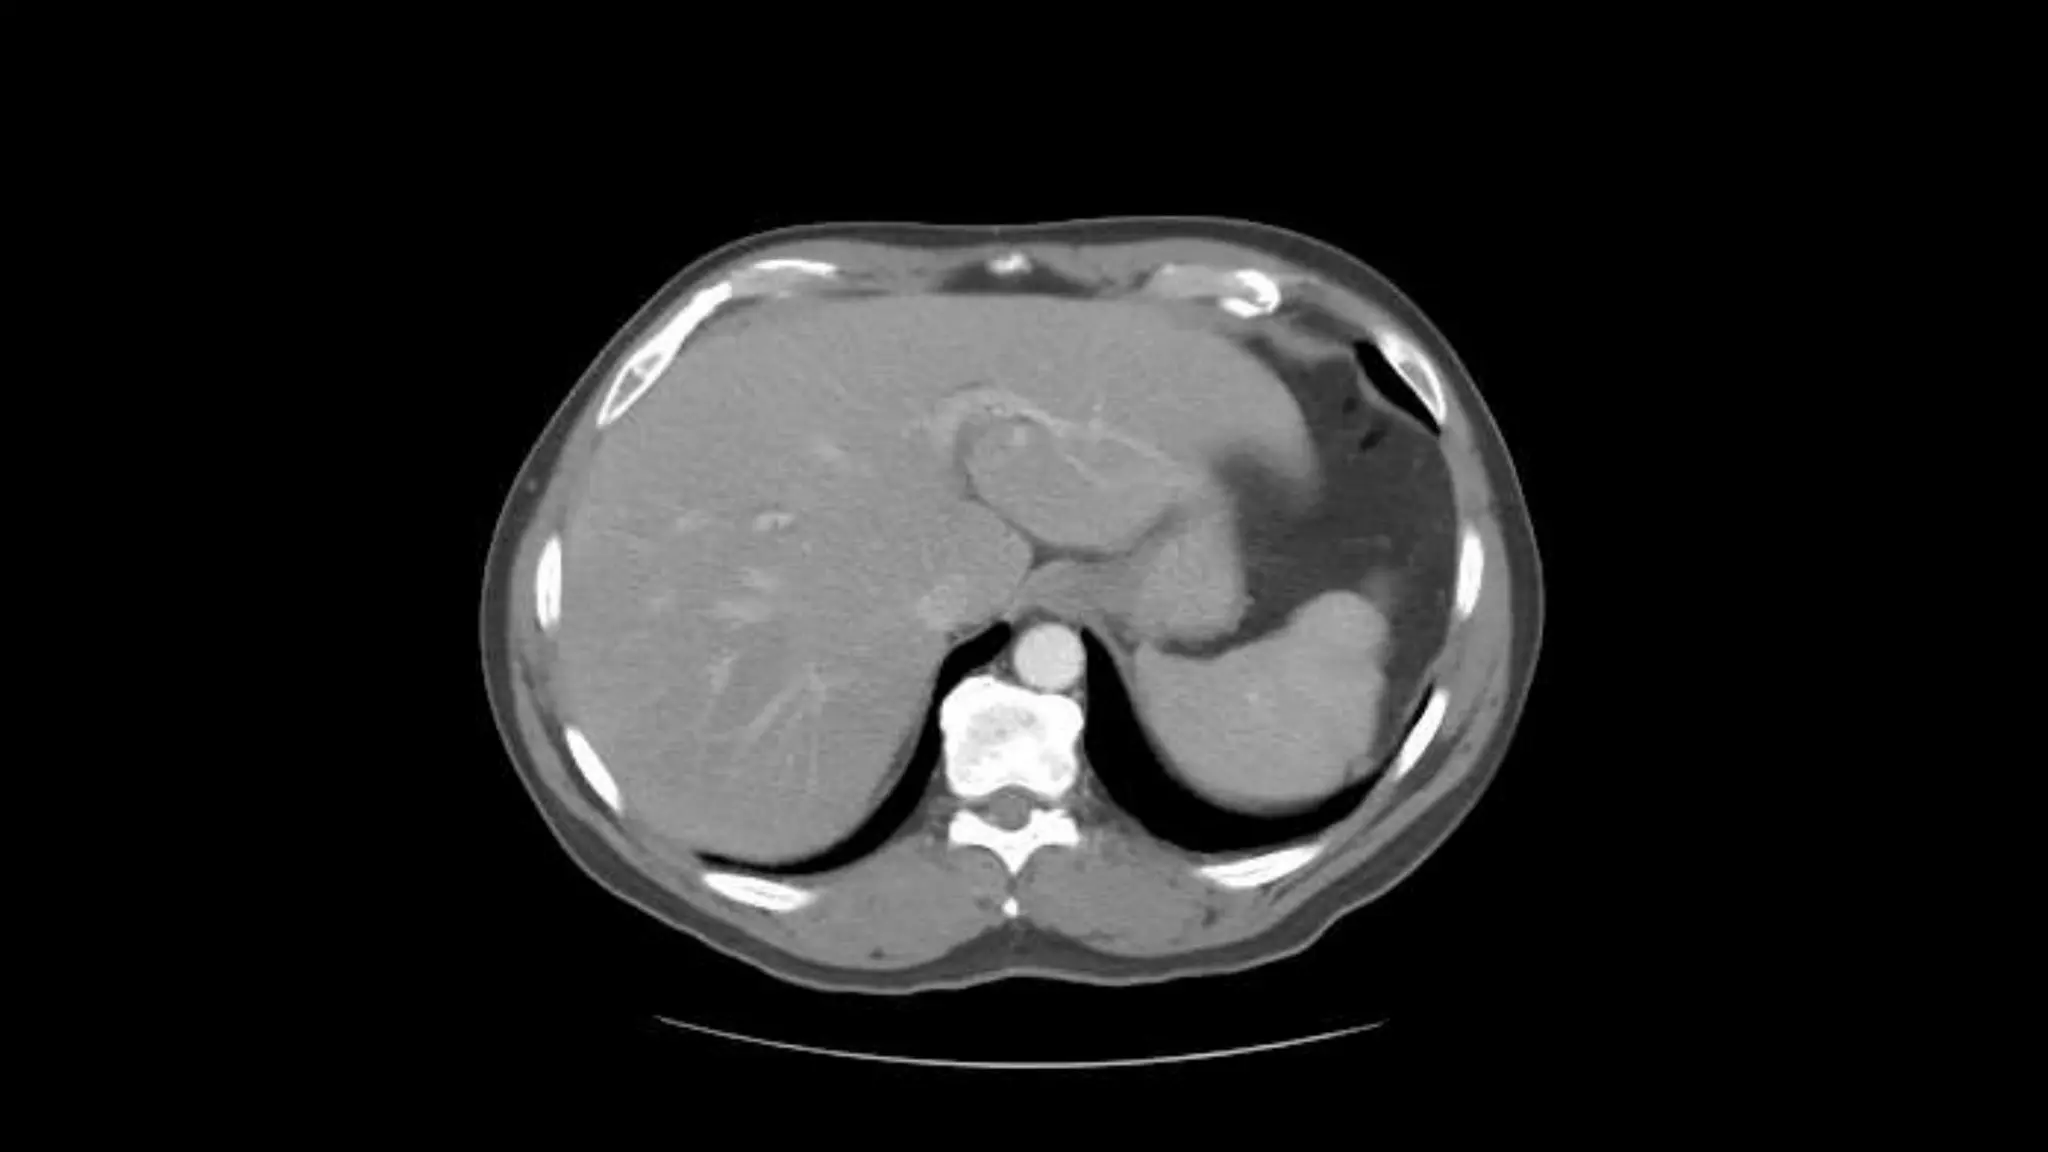

The outline of the Inferior Vena Cava is more

distinct in this image.

Portal Vein Branching into the Liver

Liver

Stomach

The outline ofthe Inferior Vena Cava is more distinct in this image.

Portal Vein Branchinginto the Liver Liver Stomach